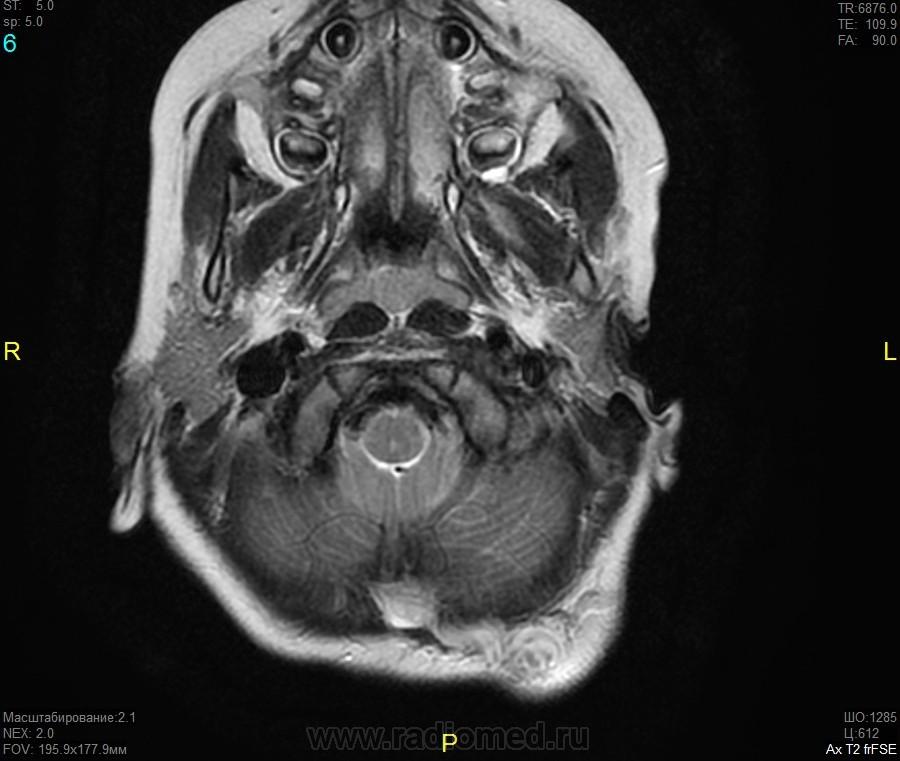

Уважаемые коллеги! Прошу консультативной помощи. Про пациента известно: девочка (7 лет), в анамнезе 2,5 года назад травма головы. Не диагностировалась. Периодически жалобы на болезненность при пальпации затылочной области(((((

Напоминает сосудистую структуру.Может, какая-нибудь лимфангиома?Видела на передней поверхности шеи, на задней - нет.

как будто связь с ликвором имеется.  Дополнил бы венографией, и FatSat"ом ну и контрастом, конечно.

Сегодня в ходе разговора с мамой девочки, выяснилось, что и у мамы есть подобное "образование". С ее слов, несколько лет назад ей делали пункцию для исключения онкологии. Результат пункции: содержится нервная ткань и лимфоциты ( опять же никаких документов я не видела). То есть можно говорить о наследственном характере.

Нейрофиброма вполне может быть. Плексиформная. Проверить на нейрофиброматоз. Я видел такой же структуры и локализации. Пятен на коже нет? Вообще на теле? И нет ли чего похожего в позадиглоточном пространстве?

есть похожее образование в позадиглоточном пространстве)

многоузловое образование  исходящее из задней части предпозвоночного пространства с переходом на подкожную жировую клетчатку головы!шваннома ,нейрофиброма и их злокачественные аналоги